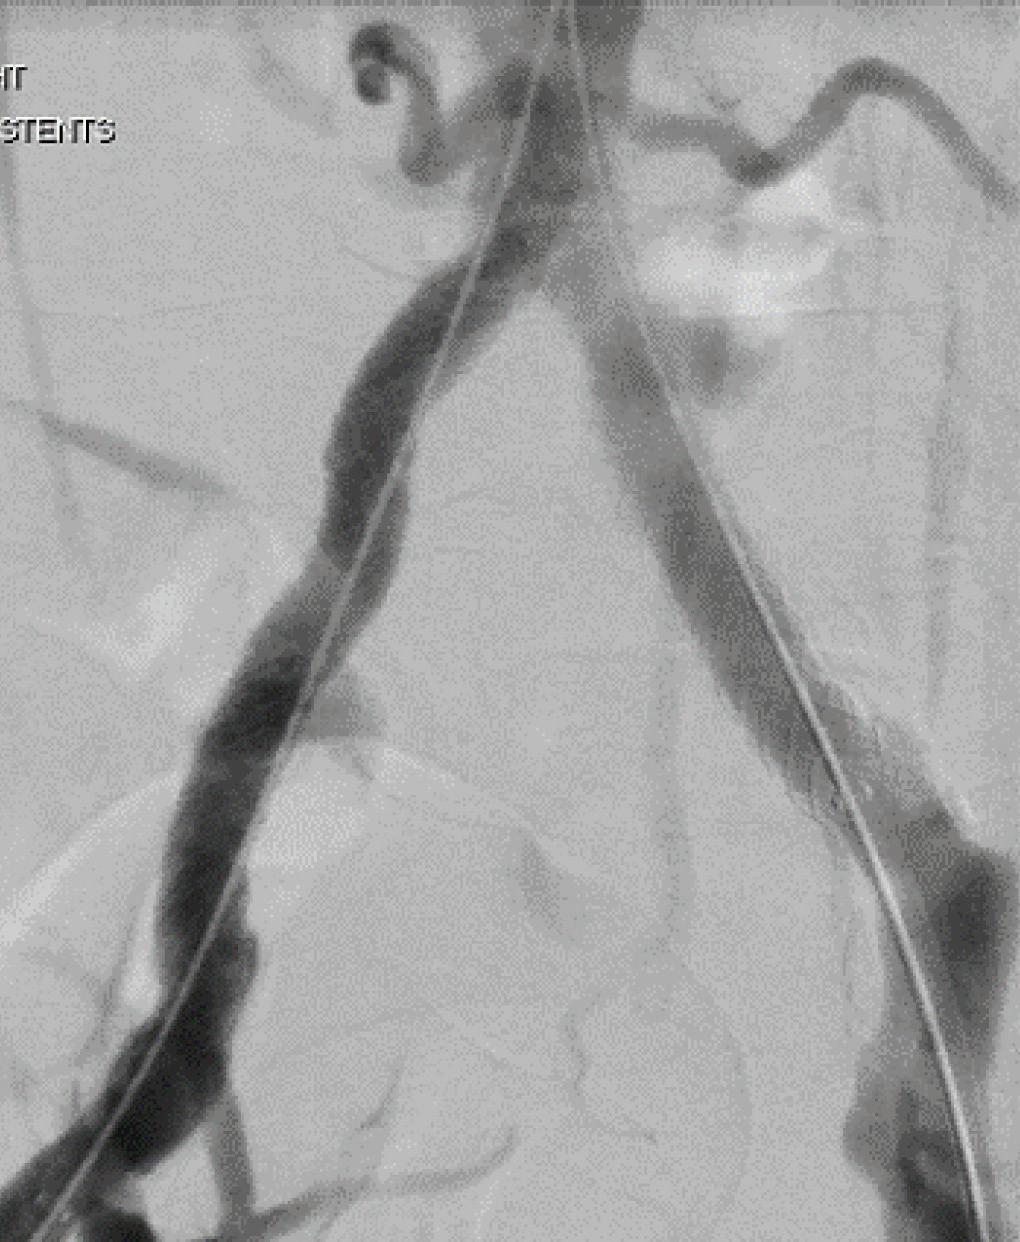

Behind the procedure: Removing in-stent thrombosis with the RevCore

Thrombectomy Catheter

For patients with in-stent thrombosis (IST), one of the most critical unmet needs has been an effective method to remove acute-to-chronic material. Here, Rishi Roy, MD, a vascular surgeon at Advanced Vascular & Vein Associates in Flowood, Mississippi, discusses his experience with the first mechanical thrombectomy device to be able to do so—the RevCore thrombectomy system. RevCore is a minimally invasive, over-the-wire device indicated to treat thromboemboli in the peripheral vasculature, including venous stents. It includes a catheter with an expandable element for venous stent treatment. It also has a reinforced catheter shaft for precise movements and a diameter-control knob for adjusting the element to treat vessels 6mmplus and venous stents from 10–20mm.

A FlowTriever catheter (Inari Medical) was advanced over a stiff wire to the infrarenal segment of the IVC, and two of the catheter’s XL disks were deployed. From the right side, a stiff wire was advanced to the IVC via a Bern catheter (Boston Scientific), followed by an Amplatz wire. The catheter was removed, and then a 16F sheath was placed.

IVUS was performed in the IVC, revealing that the stent extended into the very distal IVC; no stenosis was seen. IVUS of the right common iliac vein (CIV) showed overlapping stents but no stenosis. A venous ultrasound probe inserted to the level of the right EIV showed 50–60% stenosis. IV heparin was administered.

The RevCore catheter was advanced over the Amplatz wire to the right EIV, and the coring element was deployed within the stent in an unexpanded state. The coring element was then slowly enlarged and rotated, loosening the material within the stent. RevCore was then withdrawn and cleaned. A Triever16 Curve catheter (Inari Medical) was advanced and suction thrombectomy performed, removing a combination of subacute and chronic thrombotic material (C). Balloon venoplasty of the stented portion of the right CFV, EIV and CIV was performed with an 18mm noncompliant balloon.

Initial

Case report: Complete thrombus extraction after severe right EIV stent stenosis

Patient history

A man in his mid-50s presented with ulceration and swelling in his right foot with the intention to transfer care. Several months prior, a right external iliac vein (EIV) to right common femoral vein (CFV) stent had been placed. A venous duplex ultrasound study showed proximal stent occlusion and non-occlusive venous thrombosis in the left proximal femoral, popliteal, posterior tibial, and gastrocnemius vessels, as well as thrombosed varicosities. Right lower extremity venography and intravascular ultrasound (IVUS) performed two-and-a-half weeks later confirmed 65% stenosis of the left EIV stent (image A). An in-hospital mechanical thrombectomy and balloon angioplasty procedure was planned.

Procedural overview

The patient was positioned supine and ultrasound guidance was used to access the right CFV. A J-wire was advanced into the IVC. An 8F sheath was placed and a venogram showed stenosis within the right EIV stent (B). Similarly, access was gained to the left CFV, and a J-wire was advanced into the IVC. An 11F sheath was placed and a venogram confirmed there was no stenosis in the selected segments.

Additional passes with the Triever16 Curve catheter were conducted along the right iliac segments and within the IVC, removing thrombotic material that had been captured by the FlowTriever XL disks. Thrombus capture with either FlowTriever XL disks or the Protrieve sheath is critical to the RevCore procedure. Blood was returned to the patient using FlowSaver.

A final IVUS showed nearly 100% lumen gain, restoring the right EIV to CFV in-stent diameter to 16.4 mm (D). A final venogram demonstrated appropriate flow through the right CFV, EIV, CIV and IVC, and resolution of the stenosis within the right EIV (E). The FlowTriever disks and all other devices were removed, and manual pressure was held.

Total procedure time: 40 minutes. Estimated blood loss: <50mL. The patient tolerated the procedure well. He was discharged on dabigatran the following day. At four-week follow-up, stent patency was maintained per venous duplex ultrasound, and the patient’s right lower extremity pain and edema had improved. Progress was also seen in a previously non-healing ulceration of the right foot.

He will continue wound care and daily medication and return every six months for repeat imaging.

Conclusion

Use of the novel RevCore system ( F) allowed for thorough extraction of in-stent thrombosis and complete lumen restoration post-thrombectomy, with sustained patency and symptom relief at follow-up. The results show promise for improving quality of life in patients who had exhausted their treatment options previously.

Rishi Roy IVUS confirmed the IST (A). Preprocedure venogram demonstrated instent thrombosis and impaired flow (B). Extracted thrombotic material (C). Postprocedure IVUS confirms stent patency (D). Postprocedural venogram confirms patency (E). RevCore Thrombectomy Catheter with expandable coring element (F)